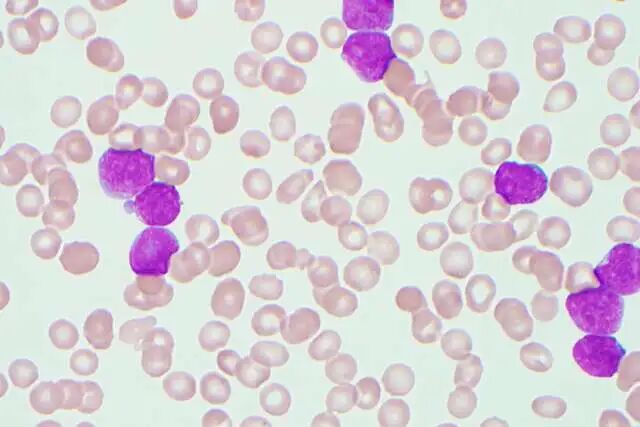

白血病:切断癌细胞的”能量命脉”

2025 年,UCLA Health 的科研团队在一种长期被认为”难以攻克”的侵袭性白血病机制上取得突破。

研究人员发现了一种全新的化合物,能够精准干扰为急性白血病提供能量的关键蛋白质。

这一策略如同切断敌军的补给线,不仅抑制癌细胞生长、诱导其死亡,还能从源头减少”白血病起始细胞”,显著降低复发风险。